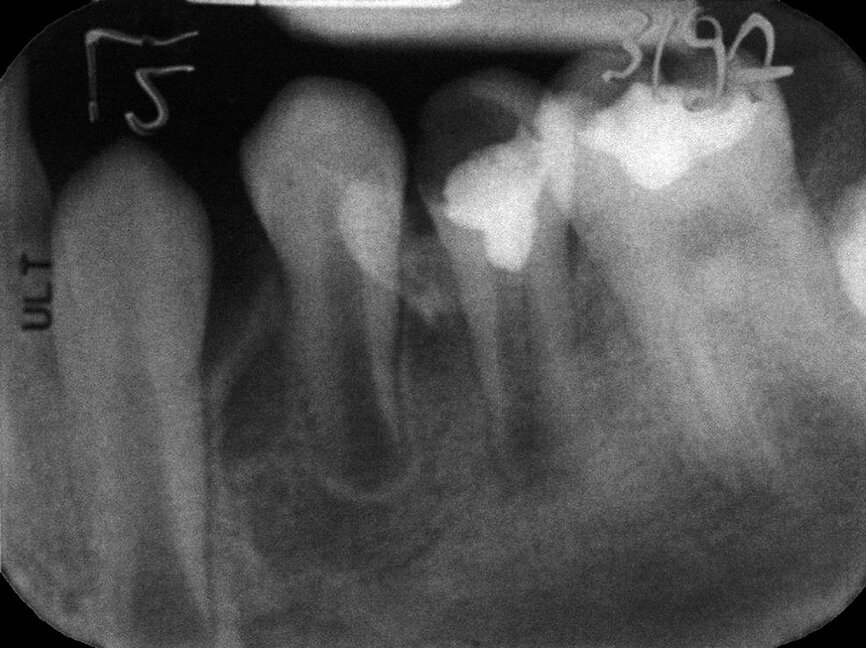

Case 2: Male (born 28 December 1980): Tooth 14

Fig. 4a: 18 August 1989 ante vitalextirpation.

Case 2: Male (born

28 December 1980): Tooth 14

Fig. 4b: 18 August 1989 post vitalextirpation.

Fig. 4c: 16 January 2004 status.